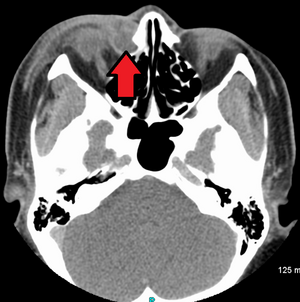

حالة التهاب الكيس الدمعي كما يظهر في التصوير الطبقي المحوسب